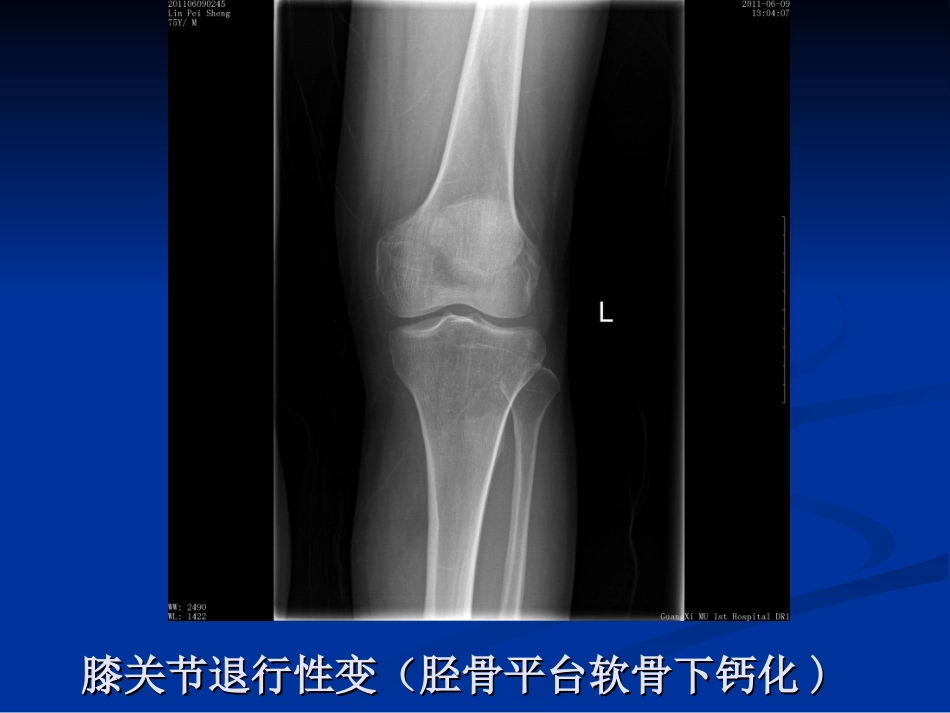

膝关节骨性关节炎膝关节骨性关节炎昌吉州中医院针灸科昌吉州中医院针灸科孙存海孙存海膝关节退行性变(胫骨平台软骨下钙化膝关节退行性变(胫骨平台软骨下钙化))膝关节退行性变膝关节退行性变((骨赘形成骨赘形成))膝关节退行性变(半月板钙化、膝关节变膝关节退行性变(半月板钙化、膝关节变形)形)在膝骨性关节炎的初期,由于大部分症状多为在膝骨性关节炎的初期,由于大部分症状多为隐匿性,即使疼痛也是比较轻微或时好时坏,因隐匿性,即使疼痛也是比较轻微或时好时坏,因此大部分病人并不在意。而恰在此时,由于一些此大部分病人并不在意。而恰在此时,由于一些不当的生活方式或工作习惯常常导致本病的进一不当的生活方式或工作习惯常常导致本病的进一步发展。到了膝关节骨性关节炎病变的中晚期,步发展。...